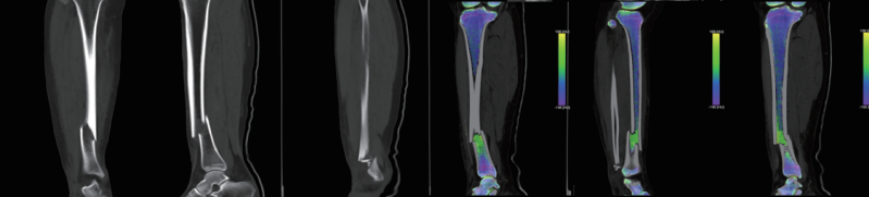

?雙能量成像技術:具有定量及成分分析功能,可用于痛風石檢測,結石成分分析,骨髓顯像等;

案例圖

痛風石檢測

骨 髓 顯 像